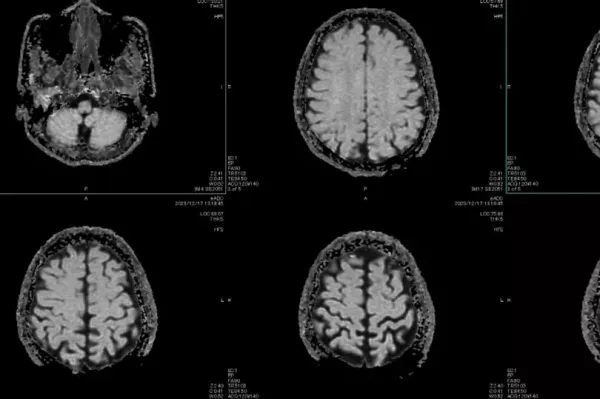

Unlike many other neurological disorders, FND describes changes in how the brain network works rather than alterations to the brain's structure. This can significantly impact a person's daily life, with signs often including seizure-like episodes, movement difficulties, speech challenges, and pain, among other symptoms, according to the National Institutes of Health.